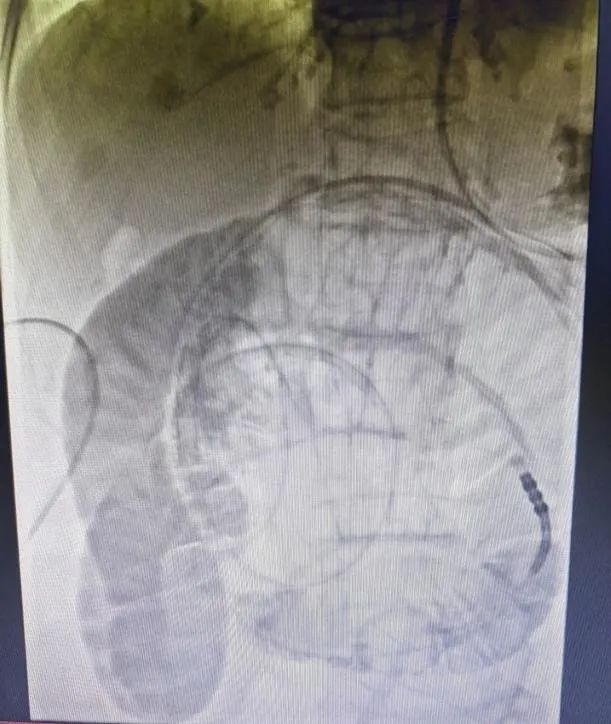

肠梗阻导管置入时造影片

案例:患者,女,78岁,因“反复腹部胀痛伴肛门停止排气排便3年”入院,既往有阑尾切除术、输尿管结石切开取石术、输卵管结扎术、鼻咽癌放疗史,有多次肠梗阻住院保守治疗史,结合CT等检查,诊断为粘连性肠梗阻,入院后禁食、解痉、抗感染、补液等对症支持治疗后,症状未见明显缓解,且腹胀逐渐加重,在DSA下消化道造影及肠梗阻导管置入,术后第二天梗阻缓解,肛门排气排便,从而进食,待肠道功能完全恢复后择期行腹腔镜下肠粘连松解术,术后6天治愈出院。

肠梗阻是常见的外科急腹症之一,任何原因引起的肠内容物通过障碍统称肠梗阻,其不但可引起在肠管形态和功能上的改变,还可导致一系列全身性病理生理改变,严重时可危及病人的生命。肠梗阻的治疗原则是纠正因肠梗阻所引起的全身生理紊乱和解除梗阻,包括手术治疗和非手术治疗,其中胃肠减压为非手术治疗的主要措施之一,传统的胃肠减压管只能放到胃,减压效果不够理想及迅速;而肠梗阻导管是在DSA下通过造影判断解剖及位置,利用导丝、导管技术将减压管放入小肠,同时通过导管前端水囊的重力及肠蠕动作用,将导管推致梗阻部位或者更远端,从而可快速、精准解除梗阻、缓解症状。同时此技术的运用可避免梗阻不能缓解尤其是粘连性肠梗阻患者的急诊手术,通过导管解压,促进肠道通畅及功能恢复,从而择期选择腹腔镜或开放手术解除梗阻原因,进一步降低手术风险及并发症的发生,从而达到缩短住院时间及减少创伤的效果。武宁县人民医院普外科已开展DSA下肠梗阻导管置入术,且取得较好疗效。